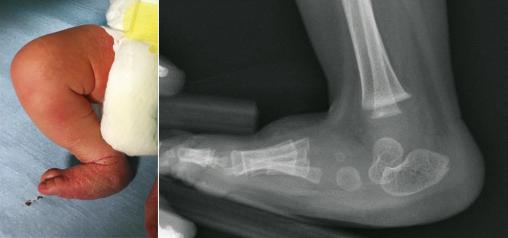

Le pied convexe est une luxation du médiotarse au niveau de l’interligne de Chopart, parfois difficile à distinguer d’une mal­position à la naissance. Cliniquement, l’arrière-pied est en équin, l’avant-pied en flexion dorsale. La plante du pied a un aspect convexe, dit « en tampon de buvard ». La tête du talus fait saillie sur le bord interne du pied. À la radiographie, la verticalisation du talus ne se corrige pas lors de la mise en flexion dorsale. Une luxation dorsale dans l’interligne de Chopart est observée.